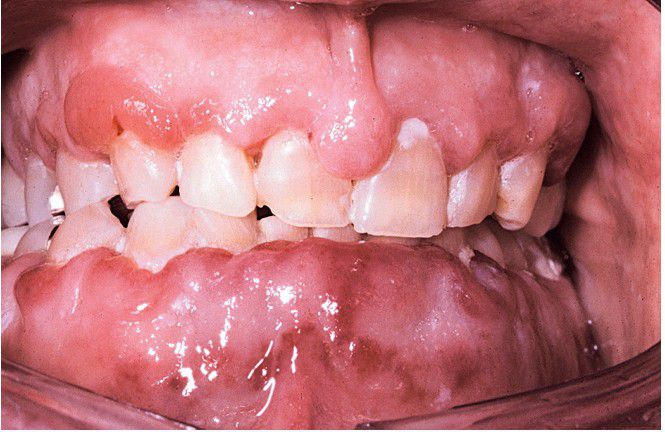

Diffuse gingival enlargement, as depicted in this photograph, may occur in leukemic patients, particularly in those with monocytic leukemia. This older man had a history of myelodysplasia for several years before the development of leukemia.